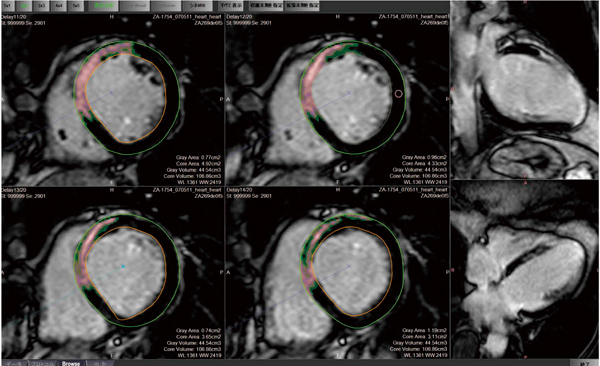

m3電子書籍 | 循環器医・放射線科医のための ゼロからわかる心臓MRI, ziostation2」の心臓領域アプリケーション - 技術解説